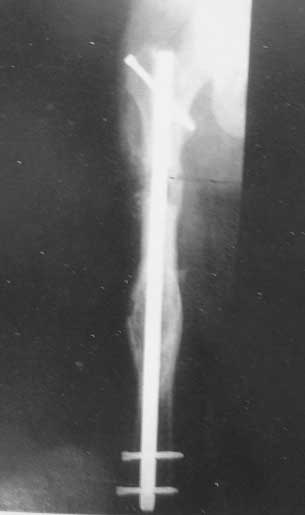

我们已经采用震波治疗了一些长骨、距骨、舟状骨、股骨颈等部位的骨折延迟愈合和骨不连,效果令人鼓舞。

95年9月开始使用超声波         95年10骨痂形成

95年11月继续愈合            96年1月31日完成桥移